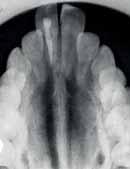

The Dental Panoramic Tomogram (DPT) confirmed the presence of all permanent teeth including the developing third molars (Figure 3). Root morphology appeared normal. The upper right central incisor had a root canal filling. The upper standard occlusal

radiograph revealed that the upper right central incisor had an adequate root filling with no periapical area. In the cephalometric assessment (Figure 4), the ANB value of 7° suggested a moderate Class II skeletal pattern. The vertical proportions were within normal values. The upper incisors were proclined at 122° and the lower incisors were of average inclination at 94°. The interincisal angle was reduced at 119°. The lower incisor to APo and the lower lip to E line were within normal limits.